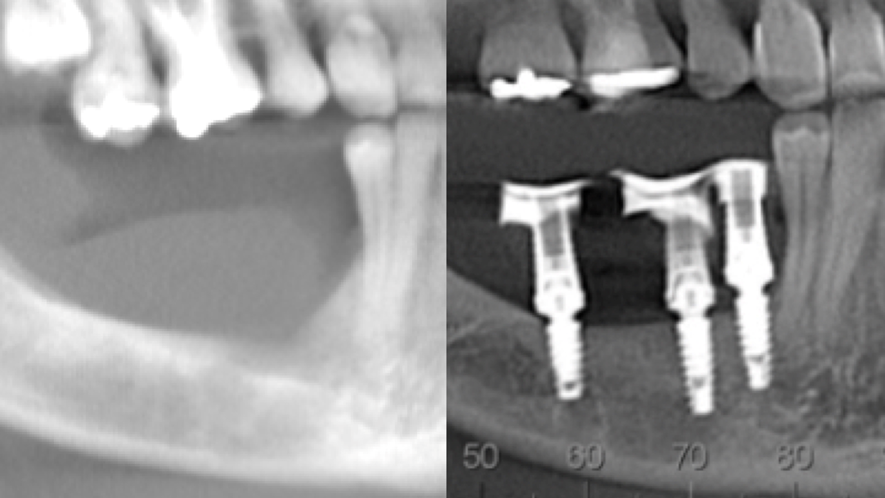

Homem de 60 anos foi encaminhado para reabilitação implantossuportada na região molar inferior direita (Figura 1). O volume ósseo remanescente tridimensional foi acessado por meio de tomografia computadorizada. Revelou uma deficiência vertical de modo que um aumento vertical foi planejado antes da colocação do implante. Seu histórico médico foi verificado e não foram encontradas comorbidades nem condições alérgicas. Não houve achados clínicos intraorais anormais, mas uma deficiência vertical na área molar inferior direita. Nenhum achado anormal foi perceptível no exame extraoral. Um enxerto autógeno em bloco ósseo dividido foi planejado para aumento horizontal e o ramo ipsilateral foi o local doador de escolha. A cirurgia foi realizada sob anestesia local com Articaína 4% e adrenalina 1:100.000. O paciente foi prescrito para enxaguar com Clorexidina 0,12% no pré-operatório, bem como tomar 1mg de Amoxicilina e 8mg de Dexametasona P.O. uma hora antes da cirurgia. Uma incisão mucoperiosteal foi realizada com bisturi número 15C desde o ramo mandibular até a borda mesiovestibular do primeiro pré-molar juntamente com uma incisão perpendicular obliquamente no vestíbulo mandibular. Após o descolamento da mucosa vestibular e liberação do nervo mentoniano, a mucosa lingual também foi descolada (Figura 2). Duas osteotomias verticais e uma horizontal foram realizadas no ramo mandibular com broca 701 para retirada do bloco ósseo necessário à reconstrução horizontal (Figura 3). Após a retirada do enxerto com auxílio de um elevador radicular, o bloco foi cortado longitudinalmente em dois pedaços finos com brocas discais e o osso esponjoso foi raspado para que pudesse ser utilizado como osso lascado (Figuras 4 a 8). Os blocos foram fixados na área edêntula. Um bloco foi fixado na face vestibular e o outro na face lingual. Cada um deles foi fixado com dois parafusos de osteossíntese de 1,5 mm e o osso lascado foi inserido no espaço entre eles (Figuras 9 e 10). A ferida foi fechada com fio de polipropileno 5-0, que foi retirado após 15 dias (Figura 11). A cirurgia cicatrizou sem intercorrências e o paciente recebeu prescrição de amoxicilina 500 mg P.O. a cada oito horas durante sete dias e ibuprofeno 600 mg a cada seis horas durante cinco dias.

Quatro meses depois foram inseridos dois implantes cônicos 3,5 x 9mm (CM Due Cone Implacil De Bortoli) na área enxertada e depois mais seis meses para instalação de coroas provisórias (Figura 12).